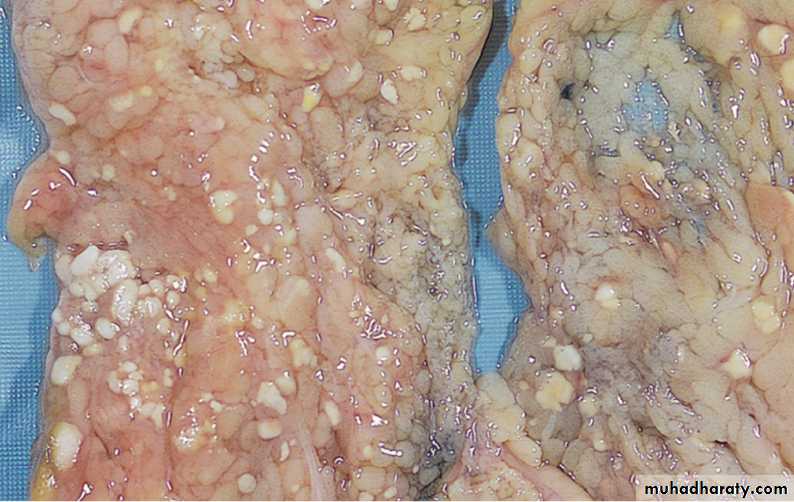

5- Fat necrosis, refers to focal areas of fat destruction, resulting from release of activated pancreatic lipases into the substance of the pancreas and the peritoneal cavity. This occurs in acute pancreatitis. In this disorder, pancreatic enzymes that have leaked out of acinar cells and ducts liquefy the membranes of fat cells in the peritoneum, and lipases split the triglyceride esters contained within fat cells. The released fatty acids combine with calcium to produce grossly visible chalky white areas (fat saponification), which enable the surgeon and the pathologist to identify the lesions . On histologic examination, the foci of necrosis contain shadowy outlines of necrotic fat cells with basophilic calcium deposits, surrounded by an inflammatory reaction.

15

The areas of white chalky deposits represent foci of fat necrosis with calcium soap formation (saponification) in the mesentery.